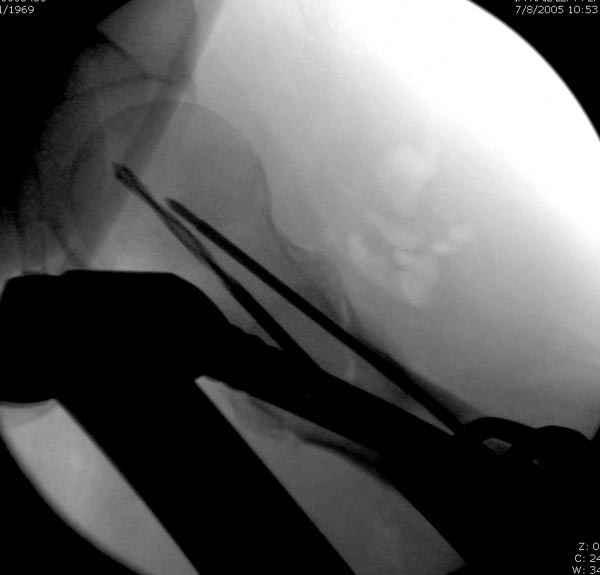

Как раз недавно у меня был примерный случай: больному 36 лет, поступил ночью, травма в результате мотоциклетной аварии, кроме чрезвертельного и спирального перелома левого бедра имеется переломы костей предплечья с этой же стороны. Скелетное вытяжение, а на следующий день больной про оперирован на ортопедическом столе с дистракцией. Чтобы не расколоть чрезвертельный перелом провели временную спицу ближе к переднему кортексу, из малого разреза костодержатель для репозиции, а фиксацию провели антиградным штифтом. Этапы операции на снимках.

Да, сейчас это и у нас самый напрашивающийся выбор. Сделали гвоздем ChM, картинки в приложении.